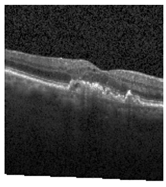

Figure 2 [26] shows the different diseases considered in this study. CNV, depicted in Figure 2a, arises from the emergence of fresh blood vessels in proximity to the choroid. CNV is caused by flaws in the innermost section of the choroid known as Bruch’s membrane, along with conditions like severe nearsightedness and heightened vascular endothelial growth. DME, Figure 2b, primarily affects individuals with diabetes. It leads to vision distortion as fluid accumulates in the macula. This accumulation impairs cone cells’ light-sensing abilities, causing blurred vision. DME arises from the expansion of blood vessels at the posterior region. In Figure 2c, we can observe Drusen, a condition primarily linked to the aging process. It involves the accumulation of yellow extracellular particles between the Bruch’s membrane and the retinal pigment in the eye. Drusen has the potential to hinder the transport system, which could lead to a deprivation of oxygen for the cone cells responsible for colour vision, ultimately resulting in their deterioration.

Figure 3. Illustrative examples from the retinal image dataset are presented. Figure (a) showcasing Choroidal NeoVascularization, characterized by the presence of neovascular membranes (indicated by white arrowheads) along with associated sub-retinal fluid (marked by arrows). Figure (b) illustrates Diabetic Macular Edema, which manifests as intra-retinal fluid associated with retinal thickening (denoted by arrows). Figure (c) displays multiple instances of drusen (highlighted by arrowheads), while Figure (d) illustrates a normal, pristine retina with an undisturbed foveal structure and no signs of retinal fluid or edema.